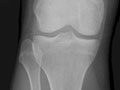

Extremity X-Ray

An extremity X-ray is a picture of your hand, wrist, arm, foot, ankle, knee, hip, or leg. It is done to see whether a bone has been fractured or a joint dislocated. It is also used to check for an injury or damage from conditions such as an infection, arthritis, bone growths (tumours), or other bone diseases, such as osteoporosis.